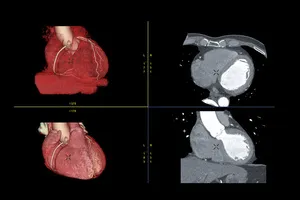

7. 경피적 관상동맥 중재술 (PCI)

막힌 혈관 부위에 작은 절개를 하고 도관을 삽입하여 풍선으로 좁아진 부위를 넓히거나 스텐트를 삽입하여 혈관을 지지하는 시술입니다.

9. 관상동맥 우회수술

막힌 혈관을 우회하여 새로운 혈관을 연결하는 수술입니다. 혈관이 여러 부위에 막혀 있거나 PCI로 해결하기 어려운 경우에 시행됩니다.